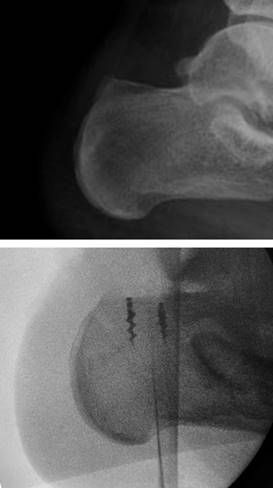

Figura 2: Control fluoroscópico del pre y postquirúrgico, se muestra resección de la deformidad y una adecuada colocación de las anclas para la reinserción del tendón calcáneo.

La técnica quirúrgica fue realizada con isquemia utilizando venda tipo Smarch, con incisión en S itálica mediante abordaje posterior tomando como referencia borde lateral de tendón aquíleo de 10 centímetros de longitud. Se disecó por planos hasta llegar a entesis, desinsertando de esa región el tendón aquíleo. Se observó tejido fibroso, se desbridó y posteriormente se realizó osteotomía de 10 milímetros, se colocaron dos anclas de 3.5 milímetros tape con agujas a 20 milímetros de distancia entre ellas y se suturó con puntos simples al cabo libre del tendón del tríceps sural. Su tunelizó borde posterior de calcáneo con broca 3.5, sosteniendo de forma temporal tendón con clavillos Kirschner. Se traspasó FiberTape con sistema Percutaneous Achilles Repair System (PARS) proximal a las suturas con técnica antidesgarro, fijando el mismo con anclas SwiveLock 2.5 milímetros (Figura 4).8 Por último, se suturaron bordes libres de tendón calcáneo con sutura de alta resistencia (Figura 5).9 Se realizaron movimientos de flexoextensión del tobillo corroborando adecuada resistencia de éste. Se corroboró adecuada colocación del material bajo fluoroscopia transquirúrgica (Figura 2).10 Se realizó hemostasia y se cerró herida con vicryl 1-0, 2-0 para tejido celular subcutáneo y nylon 3-0 para piel. Se retiró isquemia y se colocó férula suropodálica anterior en equino.